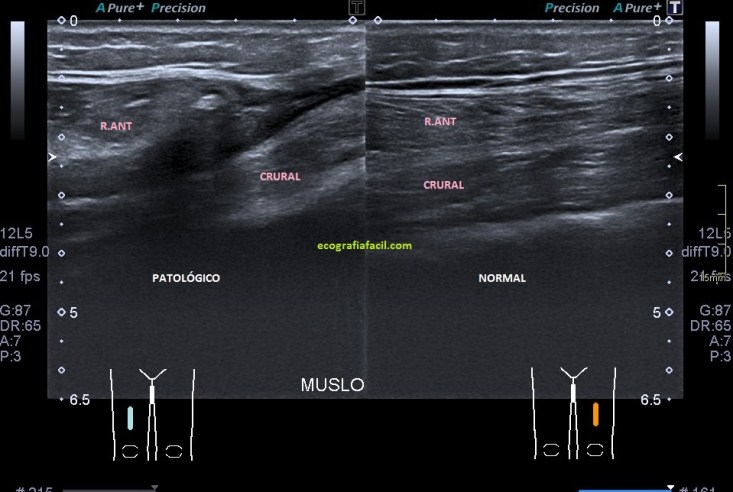

Inmediatamente exploré la misma zona del muslo contralateral, comprobando efectivamente los cambios en la ecogenicidad del músculo y cambios en el grosor, claramente disminuido en el lado afecto.

El Recto anterior afectado no se contrae correctamente (fig 6), de facto, casi no sufre variación respecto de su situación basal, el normal sufre una hipoecogenicidad aumentada, semiológicamente normal en la contracción (fig 7) y un cambio en su aspecto respecto de la situación de reposo muscular.